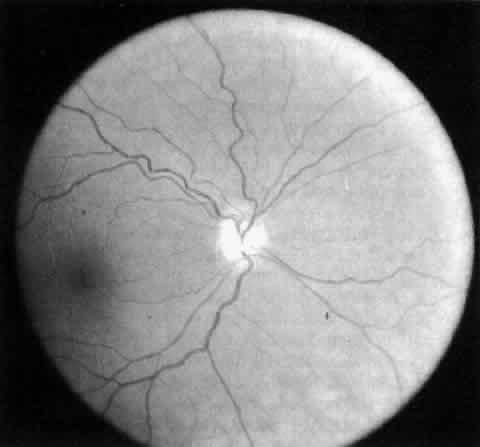

A wide spectrum of abnormalities of the fundus also is often observed.126–128 Optic nerve anomalies are common, mostly consisting of unilateral or bilateral hypoplastic optic nerves that occur in up to half of affected children (Fig. 7).126 Nystagmus and severe visual impairment are present in the most pronounced cases of optic nerve hypoplasia. The retinal vessels, mostly arteries, often are tortuous and exhibit an abnormal width and course over the retinal surface (Fig. 8).125,127

Fig. 7. Optic nerve hypoplasia in fetal alcohol syndrome. (Strömland K: Oc ular abnormalities in the fetal alcohol syndrome. Acta Ophthalmol (Copenh) 63(suppl): 171, 1985)

Fig. 8. Tortuosity of retinal vessels in the fetal alcohol syndrome. (Strömland K: Ocular abnormalities in the fetal alcohol syndrome. Acta Ophthalmol (Copenh) 63(suppl):171, 1985)

In summary, typical children with FAS are small, mildly mentally retarded, and hyperactive. They have microcephalus and a characteristic face with short palpebral fissures, a broad flat bridge of the nose, a small upturned nose, and a long upper lip with a flat philtrum. The most common ocular findings are esotropia, impaired vision, optic nerve hypoplasia, and tortuous retinal arteries.130